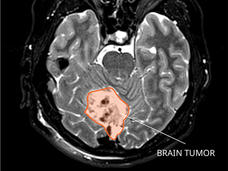

A new test could potentially be used to identify children treated for medulloblastoma who are at high risk of their cancer returning. The test detects evidence of remaining cancer in DNA shed from medulloblastoma tumor cells into cerebrospinal fluid.